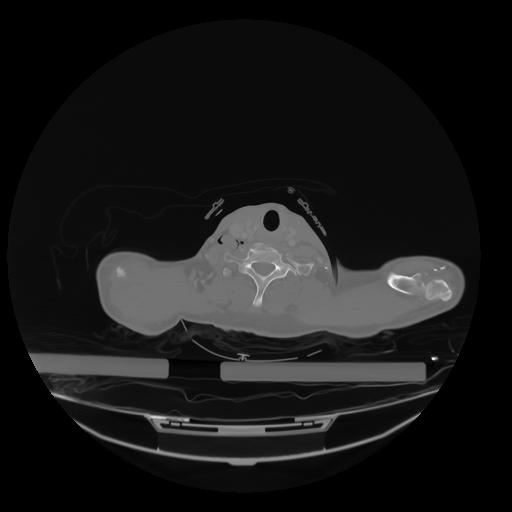

28 CUERPO,CE,Vol,2.0,CUERPO,,